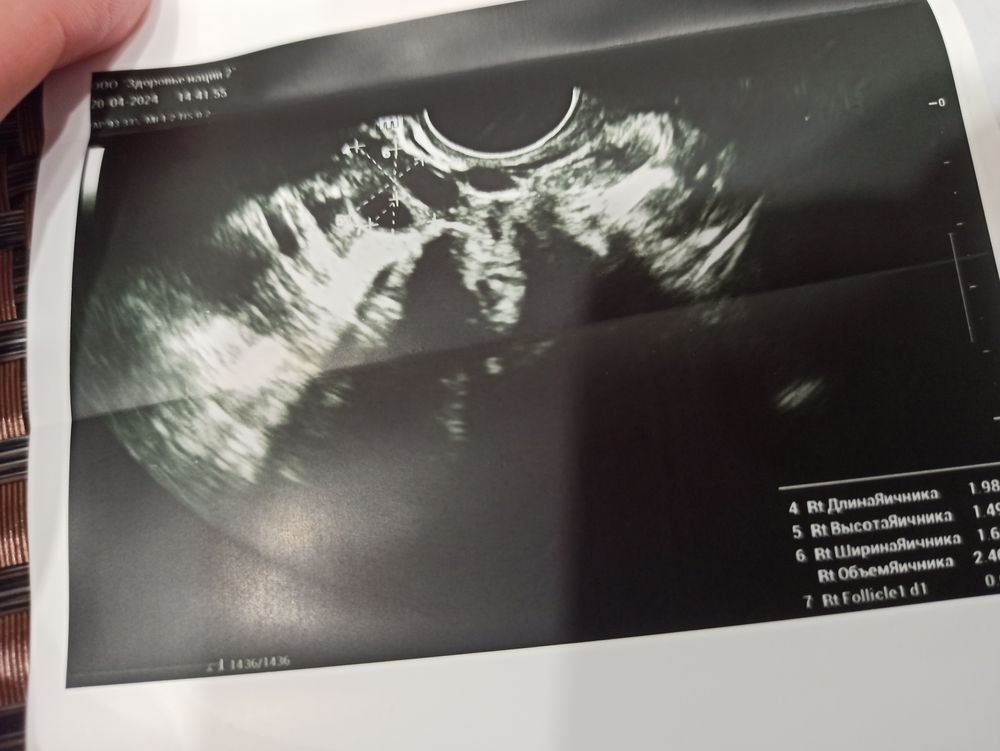

Не могу разобраться,была на узи на 17 Дц. Доктор сказал что овуляции не было, на 14 Ду был супер положительный тест на овуляцию,со всеми как должны быть выделениями яб и ТД.прилагаю фото УЗИ. Мог ли доктор ошибиться? Бывают вообще такие случаи ? Да, и на одном из яичников эндометриозную кисту обнаружили 3 см примерно(((

Оксана , на левом яичники с большей долей вероятности киста эндометриозная, есть утвердительные для этого признаки.

По данным УЗИ, овуляции у Вас не было. На УЗИ на 10 день цикла не определены доминантные фолликулы. Вторичных признаков овуляции и ЖТ не описано. Возможно был персирующий фолликул на правом яичнике, на как таковая овуляция не состоялась.